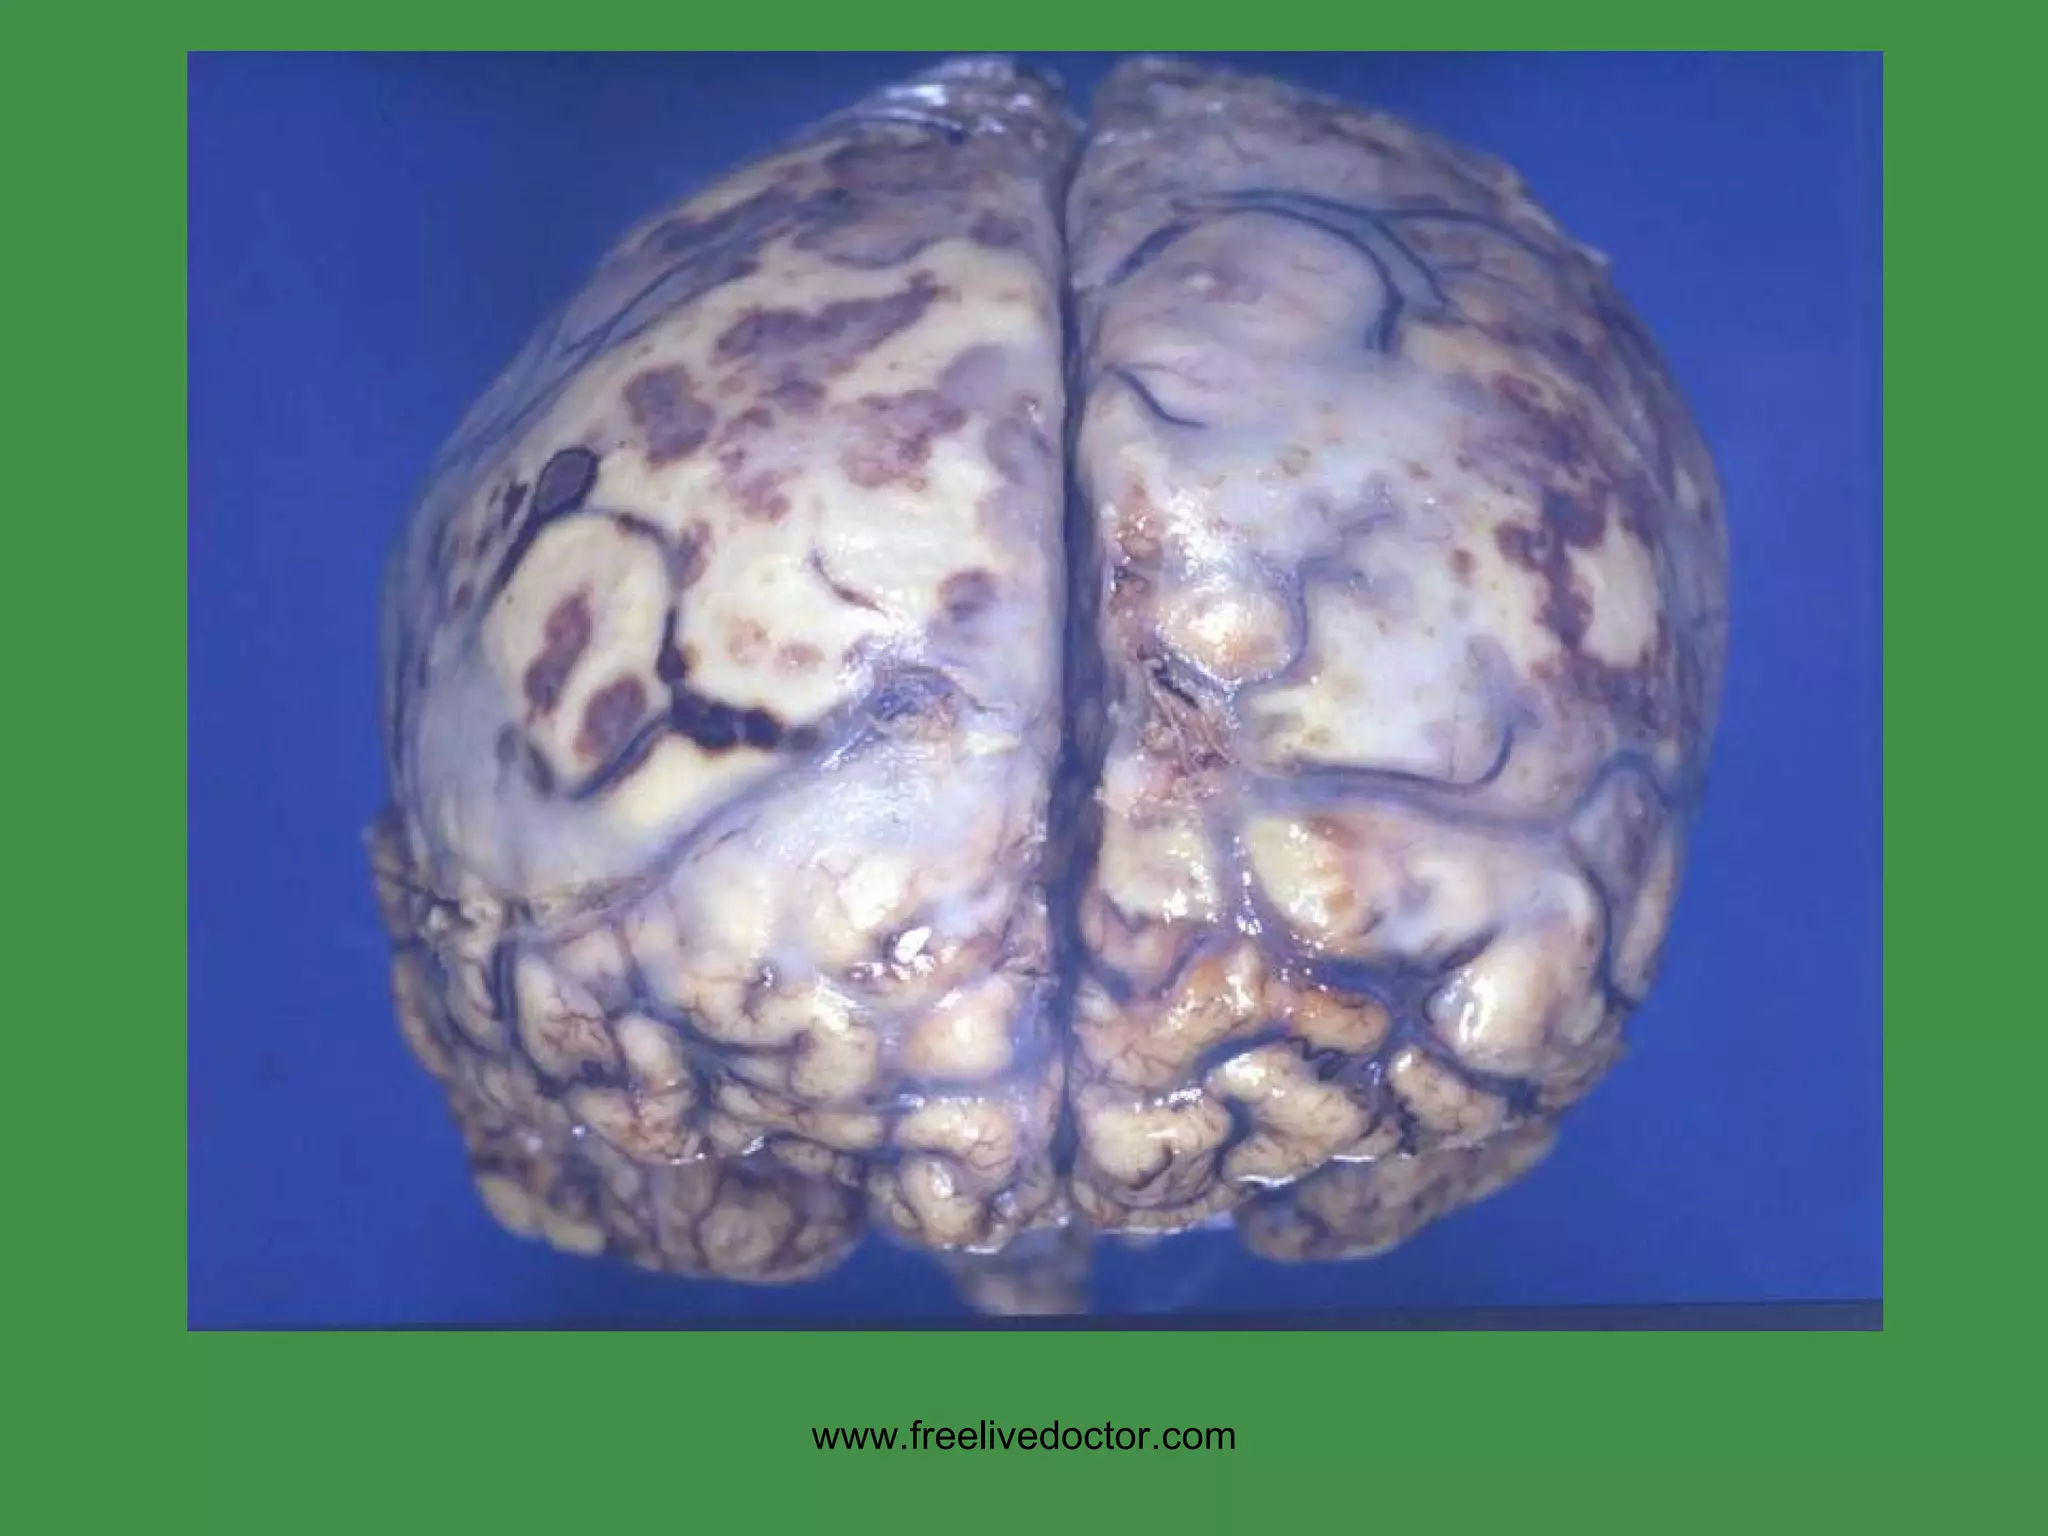

VIRAL ENCEPHALITIS PERIVASCULAR LYMPHOCYTIC “ CUFFING” www.freelivedoctor.com

PERIVASCULAR GIANT CELLS in  WHITE MATTER in HIV ENCEPHALITIS www.freelivedoctor.com

HIV www.freelivedoctor.com